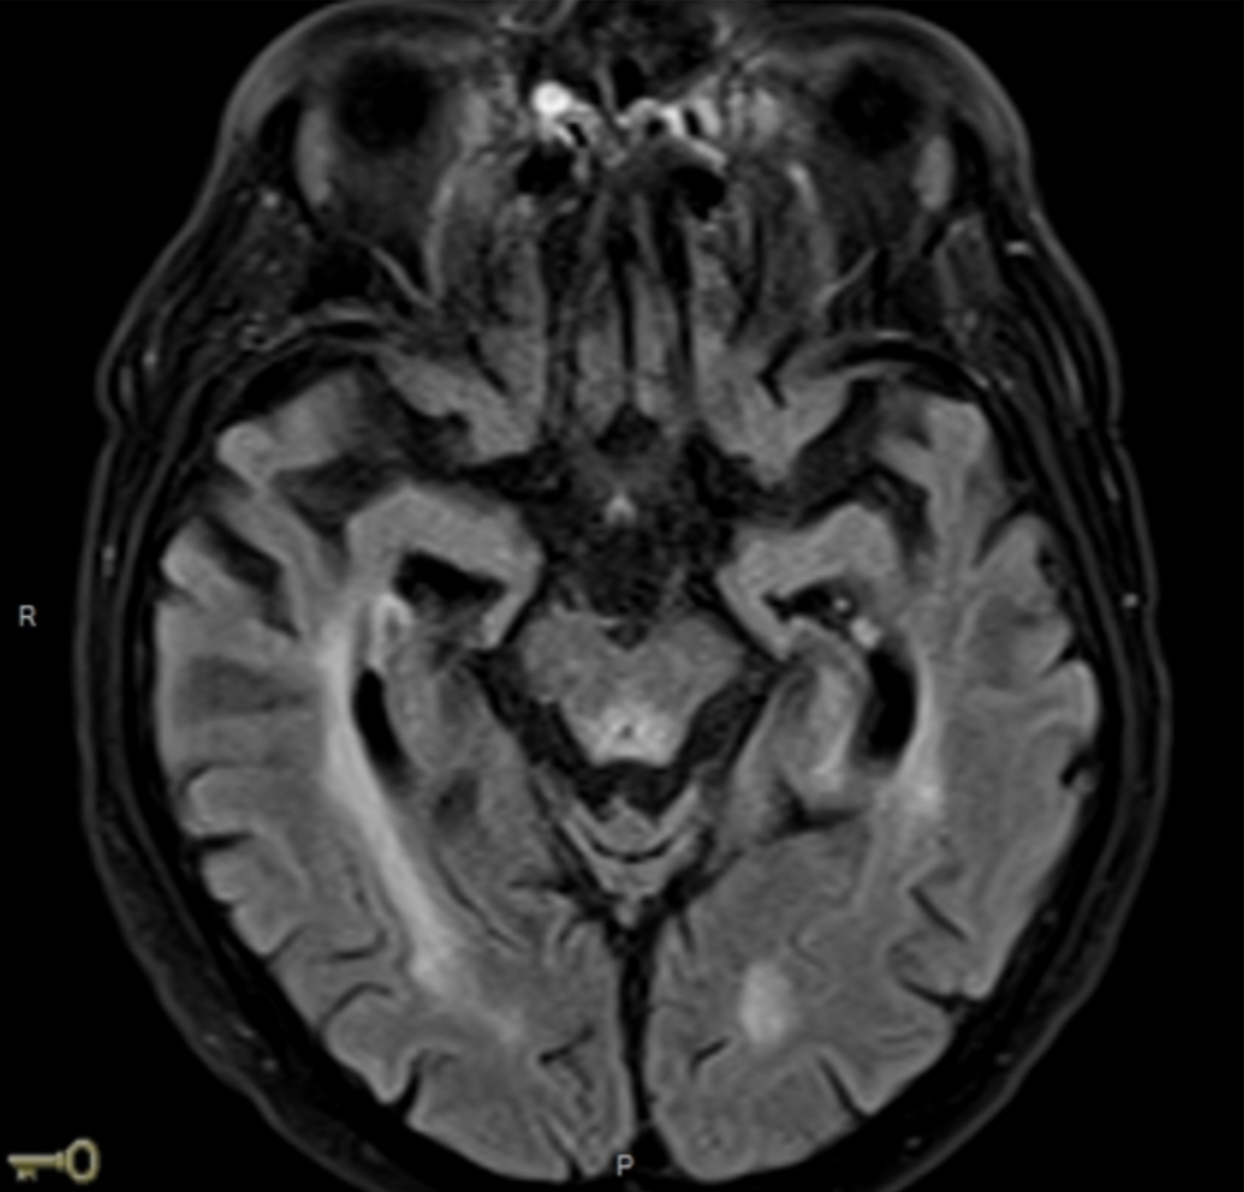

L’IRM est la suivante :

Quel est votre diagnostic ?